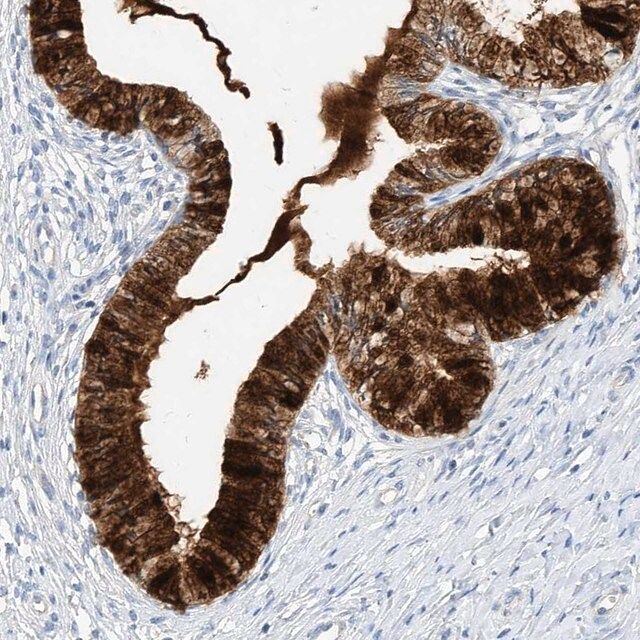

- IHC tissue array of 44 normal human tissues and 20 of the most common cancer type tissues.

| 人类蛋白质图谱编号 | HPA034584 Human Protein Atlas characterization data |